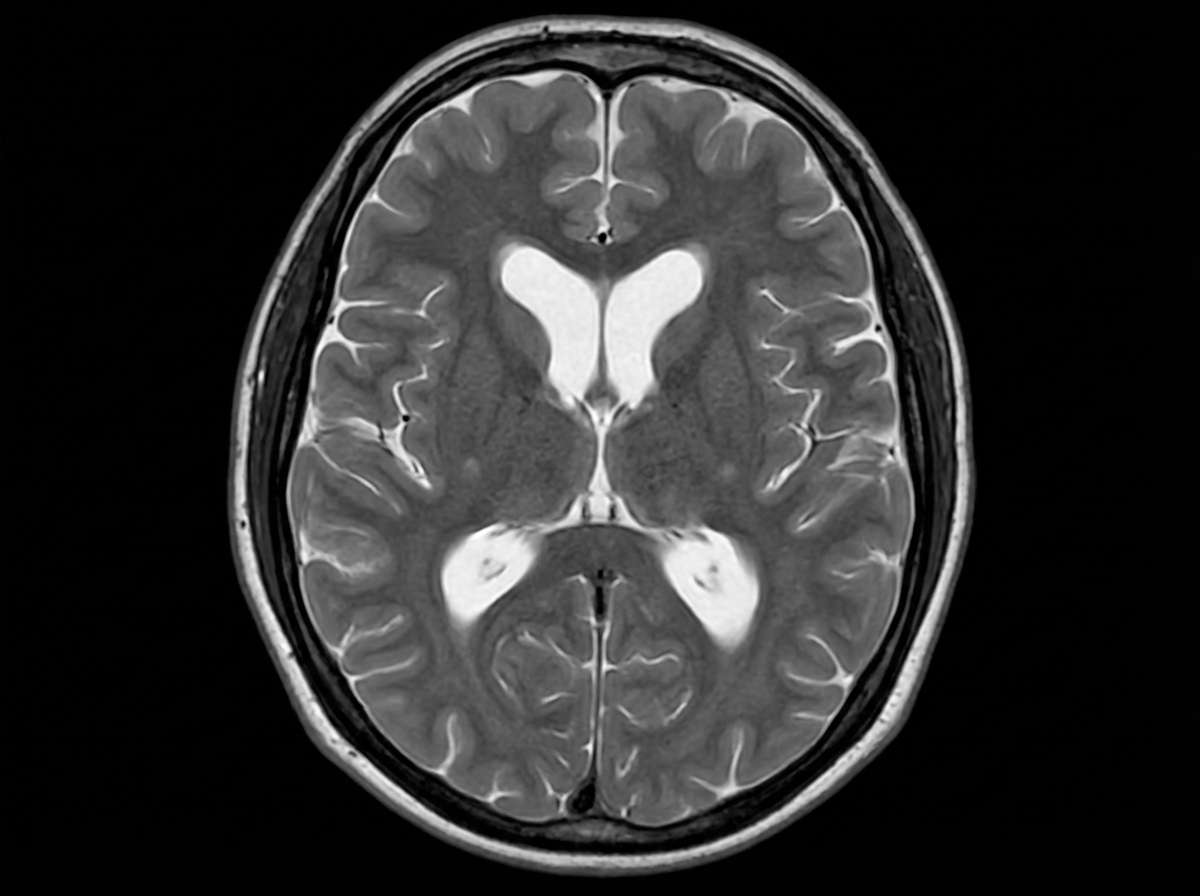

A 74-year-old man is brought to the physician by his wife for progressively worsening confusion and forgetfulness. Vital signs are within normal limits. Physical examination shows a flat affect and impaired short-term memory. An MRI of the brain is shown. Further evaluation of this patient is most likely to show which of the following findings?

A 74-year-old woman is brought to the physician by her daughter for worsening memory for the past 1 month. She can no longer manage her bills and frequently forgets the names of her children. Her daughter is also concerned that her mother has a urinary tract infection because she has had increased urinary urgency and several episodes of urinary incontinence. Vital signs are within normal limits. Physical examination shows poor short-term memory recall and a slow gait with wide, short steps. Which of the following is most likely to improve this patient's condition?